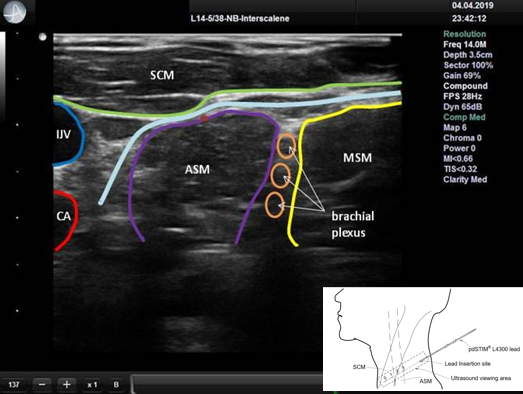

颈部超声评估患者,确保可视化和定位解剖位置,优化导线最佳放置路径。

超声波可视化床旁系统:13-16 MHz范围的探头神经模式

使用平面内技术放置经皮导线。

· 在筋膜平面内划分胸锁乳突肌浅层和前斜角肌深层,使用超声成像辅助针引导。

软电极导线直径为0.87mm,电极电荷密度限制为25μC/cm2。导线连接到一个定制的

经皮膈神经电刺激(PEPNS)控制台,在吸气过程中提供研究指定的刺激次数间隔,同时测量WOB焦耳/升(J / L)。PEPNS控制台和pdSTIM导联仅在研究用途下提供。

膈神经(PN),由暗红色点标识,位于胸锁乳突(SCM)和斜角肌(ASM)之间的内侧,臂丛的内侧和前斜角肌(ASM)的表层。SCM、ASM和中斜角肌(MSM)的边界分别以绿色、紫色和黄色显示。颈内静脉(IJV)和颈动脉(CA)也在图像中被识别。浅蓝色的线显示了引路。超声图像中左侧的大刻度线间距为5mm。右下角图像中用虚线勾勒出的方框区域是沿导线插入路径的超声观察区。插入针头时,有必要移动超声探头以保持可视化。

导线的放置采用超声技术,行平面内视觉跟踪18G×75mmTuohy尖头针。

根据制造商建议,选择理想的导线放置方法,超声下可见针穿越筋膜平面深到胸锁乳突肌(SCM)到达前斜角肌(ASM)表面。

在超声引导下,带生理盐水推注的针通过1mm的皮肤切口进入,直至尖端到达颈根部的颈内静脉和颈动脉附近,推注盐水出针。通过水分离术扩大ASM和SCM组织平面之间的距离及预期膈神经位置。当针到达位置后,经针头尖端置入导线,超声引导下退针留导线。导线被连接到PEPNS控制台获得膈神经信号。